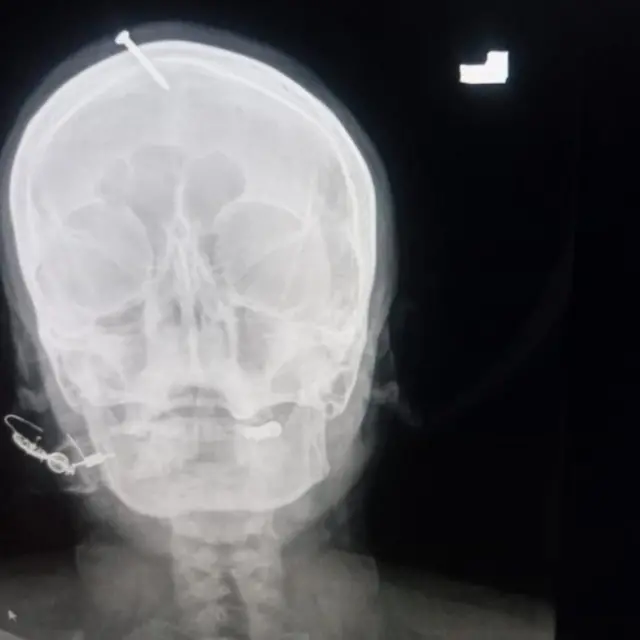

متاثرہ خاتون کو دو دن قبل رات کے وقت لیڈی ریڈنگ پشاور کی ایمرجنسی میں لایا گیا۔ خاتون بے ہوشی کی حالت میں تھیں اور ان کے ماتھے پر لگی ہوئی کیل کھوپڑی کے اندر تک گھسی ہوئی تھی جس سے خون بہہ رہا تھا اور خاتون کی حالت انتہائی تشویش ناک تھی۔

ایمرجنسی میں موجود ایک ڈاکٹر کے مطابق جب خاتون کو ان کے پاس لایا گیا تو ان کا سی ٹی سیکن کرنے کے بعد فوراً نیورو وارڈ کو ایمرجنسی کال کی گئی اور ہنگامی طور پر آپریشن کی تیاریاں کی گئیں، کیونکہ خاتون کی حالت تشویش ناک تھی اور خاتون حاملہ بھی تھی۔

ڈاکٹر کے مطابق لیڈی ریڈنگ ہسپتال کے اندر فی الفور آپریشن کر کے ان کے ماتھے میں لگی کیل کو نکالا گیا جس کے بعد خاتون کی حالت سنبھلنا شروع ہو گئی۔